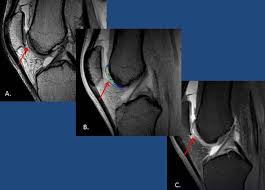

Owens uses cartimax® viable cartilage allograft to treat an articular cartilage defect in the medial femoral condyle. Surgery options include removal of cartilage, drilling to relieve pressure, bone or cartilage. The significant advantages of using a flexible reamer is the avoidance of the medial femoral condyle articular cartilage, and can curve around the medial condyle as pointed out by previous studies. Distally the linea aspera forms two ridges known as the lateral supracondylar line and the medial supracondylar line which as the name suggests, terminate just superiorly to the lateral and medial femoral condyles respectively. Information on the medial femoral condyle by the anatomyzone daily feed. Cartilage defect of lateral femoral condyle. Femoral cartilage was examined with patients in a supine position, and both knees were at maximum flexion. Carticel® is indicated for the repair of symptomatic cartilage defects of the femoral condyle (medial, lateral or trochlea), caused by acute or repetitive trauma, in patients who have had an inadequate response to a prior arthroscopic or other surgical repair procedure (e.g., debridement. In carnivores, on the caudal surface of each condyles are small facets (articular surface for lateral or medial sesamoid) for articulation with the the two sesamoid bones (fabellae) embedded in the tendons of origin of gastrocnemius. Along with a similar section of the meniscus in the lateral compartment. In 2 horses, debridement was not performed because of extensive generalized damage to the cartilage. Allograft donor medial femoral condyle (blue arrow) and medial trochlear facet (red arrow). The guide pin is in the amp, the arthroscope is in the central portal, and the right knee is flexed 100°, with the patient in the.

Recent studies suggest that surgery actually stimulates regeneration of the bone. The remaining articular cartilage thickness after resection of the posterior femoral condyle was measured and simple analysis conducted to compare conclusions: The medial femoral condyle in this patient shows mild cartilage fibrillation, while tibial cartilage is normal. It is covered by articular cartilage that. Allograft donor plugging the osteochondral lesion (blue arrow).